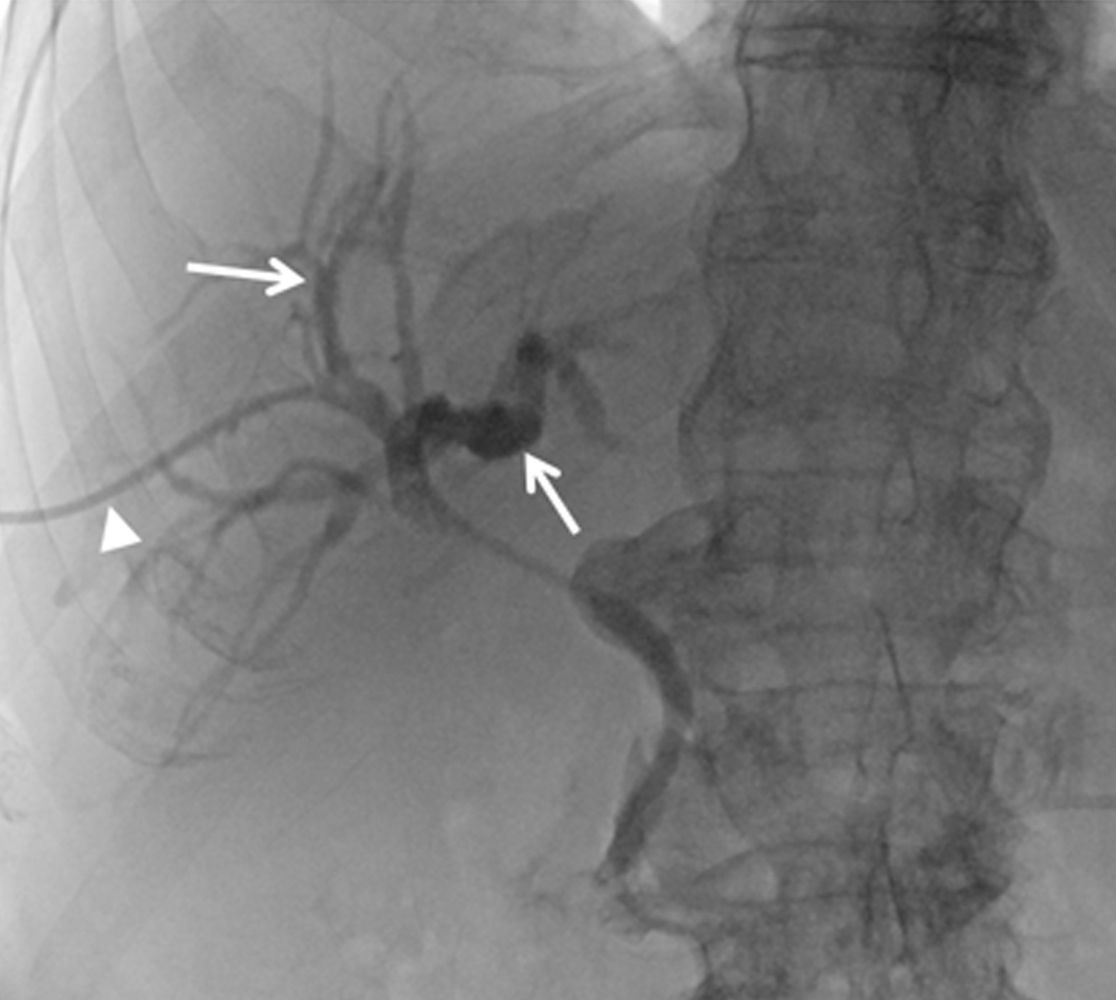

Unser Zentrum zeichnet sich weiterhin durch eine dreidimensionale bzw. räumliche periprozedurale Planung der TIPSS Anlage aus, welche ein insgesamt schonenderes Vorgehen mit verbesserten Ergebnissen ermöglicht.

Planung und Durchführung einer TIPSS Anlage.